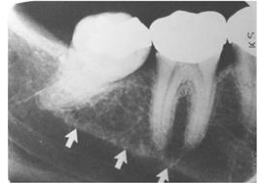

72.下圖上顎後牙區之根尖片,靠近第一大臼齒根尖處之放射線不透過性(radiopaque)影像,最可 能之X光診斷為:

(A)多生牙(supernumerary tooth) (B)竇結石(antrolith) (C)殘根(residual root) (D)牙瘤(odontoma)